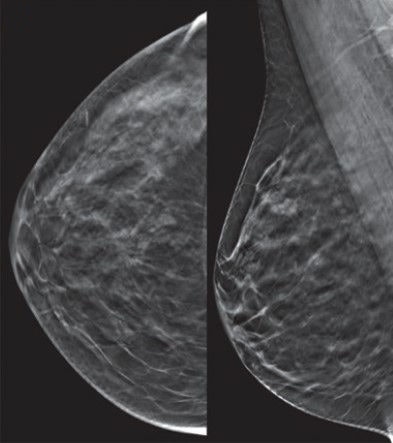

Dense breast tissue can mask breast cancer on mammography, and furthermore, the denser the breast, the greater the risk of developing breast cancer -- a fourfold increased risk, in fact. Dense breasts are so problematic that 38 states as well as Washington, DC, require some form of density information in mammography results letters sent to patients.

Considering dense breasts are harder to image on mammography and more likely to conceal breast cancer, what are physicians supposed to do? The answer: Use supplemental ABUS or breast MRI.